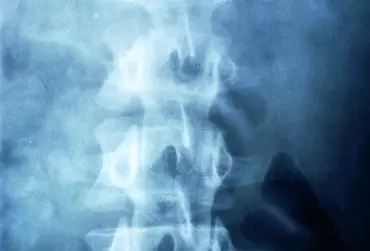

Diagnostyka różnicowa połączenia czaszkowo-szyjnego i górnego odcinka szyjnego C1/C2/C3

Połączenie czaszkowo-szyjne (cranio-cervical junction – CCJ) w sensie dosłownym tworzy ruchome przejście pomiędzy kłykciami kości potylicznej (C0) i powierzchniami stawowymi pierwszego kręgu szyjnego – atlasu (C1), ale ze względu na skomplikowaną biomechanikę ruchu w górnym piętrze szyjnym, specyfikę budowy dwóch górnych kręgów oraz specyfikę unerwienia tego rejonu, przejście czaszkowo-szyjne należy omawiać łącznie z trzema górnymi segmentami kręgów szyjnych. Strefa ta należy do najbardziej skomplikowanych ruchomych połączeń szkieletu. Przy znacznej ruchomości, jaką zapewnia, musi jednocześnie sprostać ochronie przed uszkodzeniem tak ważnych struktur, jak rdzeń przedłużony, rdzeń kręgowy, tętnice kręgowe, opony rdzenia kręgowego – stąd niespotykane w innych rejonach nagromadzenie więzadeł i błon łącznotkankowych oraz krótkich mięśni przebiegających wielowarstwowo w dość ciasnej przestrzeni.